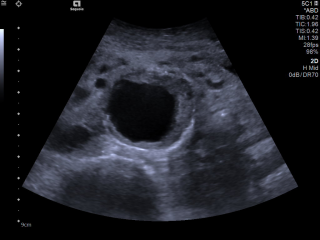

Die Ultraschalldiagnostik ist in allen Bereichen der Medizin eine der wesentlichen Säulen der bildgebenden Diagnostik und ist ein essentieller Bestandteil der täglichen Routine. Diese bildgebende Technik gehört zu der am schnellsten wachsenden Verfahren in der Medizin. Der medizinische Ultraschall, liefert in vielen Bereichen beeindruckende Fortschritte und führt zu einer Steigerung des aktuellen Wissens über moderne Diagnose- und Interventionstechniken. Für eine optimale Vorbereitung auf diesen Entwicklungstrends, Bedarfs es einer kontinuierlichen Aus- und Weiterbildung.

Während des Kurses gibt es Zeit für ein individuelles Training an den US-Geräten und für die Arbeit an klinischen Fällen - von leicht bis schwierig zu interpretierenden Fällen.

Die Übungsgruppen bestehen aus 5 Teilnehmern, die in den Grundkursen an Models und in den Folgekursen (Aufbaukurs) an Patienten ihre Untersuchungstechnik und -strategie erlernen.